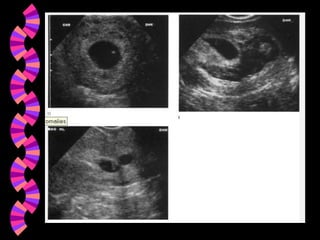

DiagnósticoAmenaza de AbortoAbortoInevitable Aborto en cursoAborto IncompletoAborto CompletoAborto Diferido - Retenido - FrustradoAborto SépticoAborto Recurrente - Aborto HabitualAborto Terapéutico